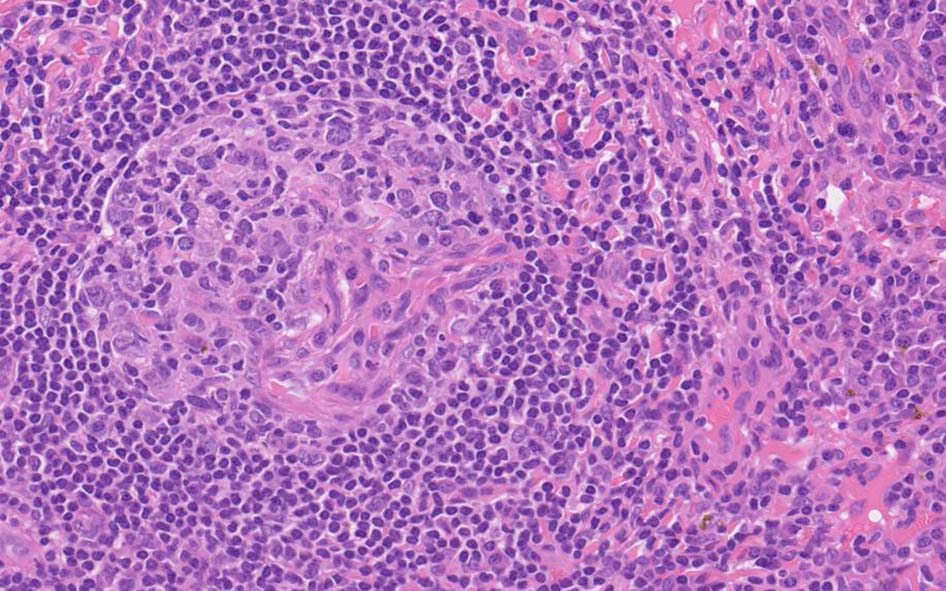

萎縮した胚中心をマントル細胞が取り囲む濾胞構造がびまん性に認められる. 濾胞間には,形質細胞が密に認められる.

萎縮した胚中心には細血管が侵入する特徴的な所見がある. (Lolli-pop germinal center)

免疫染色; リンパ節のplasma cellは多くがIgGが陽性. さらにIgG4陽性plasma cellsが多数をしめる.